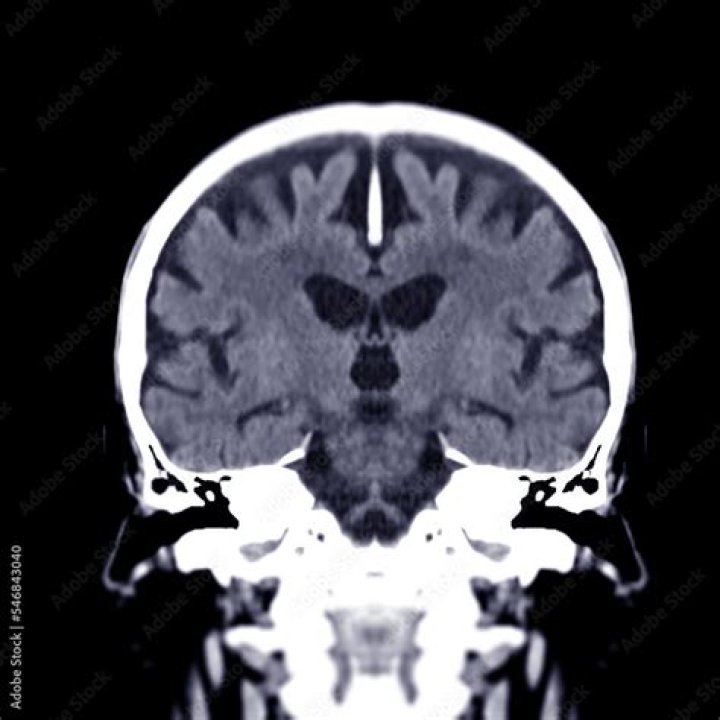

What does GREY matter do in the brain

[6] The grey matter throughout the central nervous system allows enables individuals to control movement, memory, and emotions. Different areas of the brain are responsible for various functions, and grey matter plays a significant role in all aspects of human life.

The gray matter is the areas where the actual “processing” is done whereas the white matter provides the communication between different gray matter areas and between the gray matter and the rest of the body. The neurons in the gray matter consist of neuronal cell bodies and their dendrites.

Grey matter plays a significant role in allowing humans to function normally as it allows us to control our movements, retain memories, and regulate our emotions, among many other functions. Grey matter is therefore essential for all most aspects of human life. Grey matter is formed in early development from ectoderm.